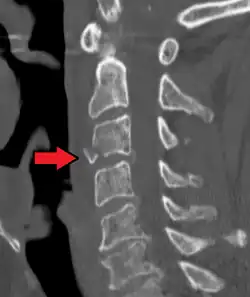

Teardrop fracture of C3 (sagittal CT)

On CT scan or X-ray, a cervical fracture may be directly visualized. In addition, indirect signs of injury by the vertebral column are incongruities of the vertebral lines,[7] and/or increased thickness of the prevertebral space:[8]